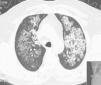

Pulmonary Alveolar Proteinosis (PAP) is a rare diffuse lung disease with three clinical forms, congenital, acquired (idiopathic) and secondary, characterized by an accumulation of large amounts of a phospholipoproteinaceous material in the alveoli due to a deficiency in granulocyte-macrophage colony-stimulating factor (GM-CSF) activity1–14 (Fig. 1). This is associated with an abnormal macrophage function and an impaired clearance of surfactant from the lungs. PAP has a prevalence of 3.7 cases per million, a male preponderance (4:1 male/female ratio) and 80% of the cases are reported during the third and fourth decade of life.6

The second patient submitted to WLL was a female, 47 years old, farmer, non-smoker, no comorbidities, with the diagnosis of PAP one month before the first WLL based on clinical, radiological and BAL features and the presence of serum GM-CSF antibodies. The clinical presentation was very similar to the first patient's, with dyspnea on exertion and a dry cough associated with respiratory insufficiency and wide bilateral crazy paving pattern opacities in the HRCT scan. After the diagnosis, a WLL was performed with instillation of 14 and 10.8L of saline into the right and left lung respectively. After a brief initial clinical improvement, she was submitted to another WLL 1.5 months later, since she had become more symptomatic and with paO2<60mmHg. With this procedure, a total of 13.5 and 10.6L were instilled into the right and left lung respectively. Four months later a third WLL was performed because of clinical deterioration and at this time 15.5 and 11.1L were instilled into right and left lung respectively (Fig. 4). After this procedure, the patient achieved clinical, functional and radiological stability.